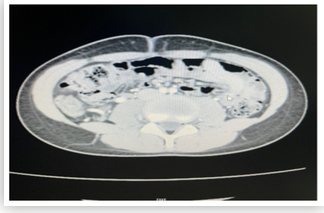

Case Report

Ovarian Juvenile Granulosa Cell Tumor in Childhood: The Importance of Early Diagnosis. Case Report

Fatma Chebab, Aida Daib, Rabiaa Ben Abdallah, Malek Boughdir, Sameh Tlili and Nejib Kaabar.